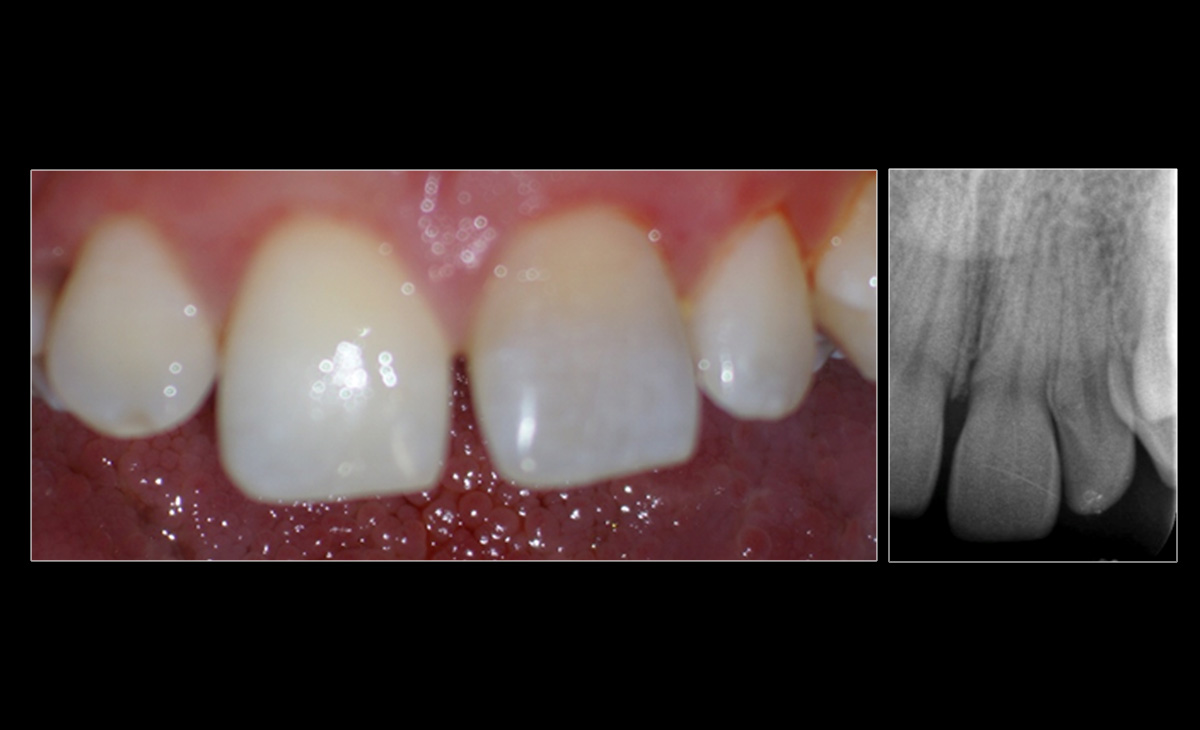

| Patient age | 23 |

| Patient sex | Male |

| Tooth | 21 |

| Treatment planned | Orthograde root canal treatment and intracoronal bleaching |

| Prognosis | Good |

| Bleach | Sodium perborate for 2 weeks |